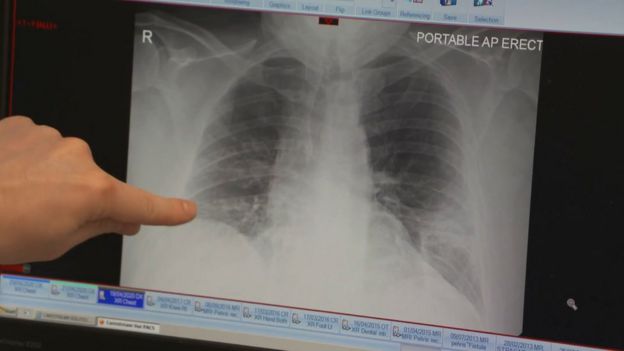

One of such patients, Amy Watson from Oregon, USA has had a fever for more than 100 days.

She is a preschool teacher who was diagnosed with COVID-19 in April, and ever since she has a constant fever that rises up to 101 degrees every afternoon.